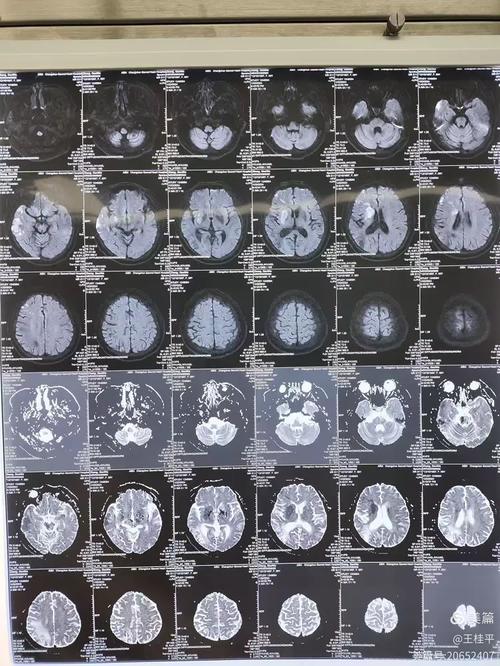

MRI (Magnetic Resonance Imaging / 核磁共振)

- 作用:是诊断早期脑梗的“金标准”。

- DWI序列 (弥散加权成像):能在脑梗发生的几十分钟到2小时内就发现异常信号,对早期脑梗的敏感性极高,如果怀疑是超早期的脑梗,医生会首选MRI检查。

- 优点:没有辐射,对软组织和病灶的显示比CT更清晰。